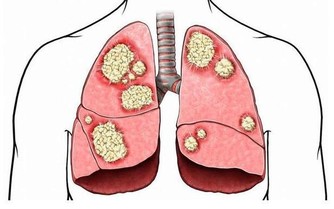

原發性肝癌是目前我國第4位常見惡性腫瘤及第2位腫瘤致死病因,嚴重威脅我國人民的生命和健康。

中華預防醫學會在《中國肝癌一級預防專家共識2018》中指出:國際癌症研究中心在進行全球惡性腫瘤負擔調查時發現,2012年全球新發肝癌病例高達78.2萬,死亡病例74.6萬,而其中50.5%的新發患者、51.3%的死亡患者都集中在中國。

更令人惋惜的是,目前中國的肝癌篩查推進工作很不理想,患者術後5年生存率也僅達12.1%,這更加突出了“肝癌防治”的必要性!而想要更有效地防治,了解肝癌的誘因,針對性地遠離危險因素則十分有必要。

三、肝癌需重視早發現早治療

肝癌的產生是肝臟長期、反复徘徊於修復和損傷之間,直到修復跟不上損傷就會發生腫瘤,一旦發生後果嚴重,所以一定要早預防、早發現、早治療。